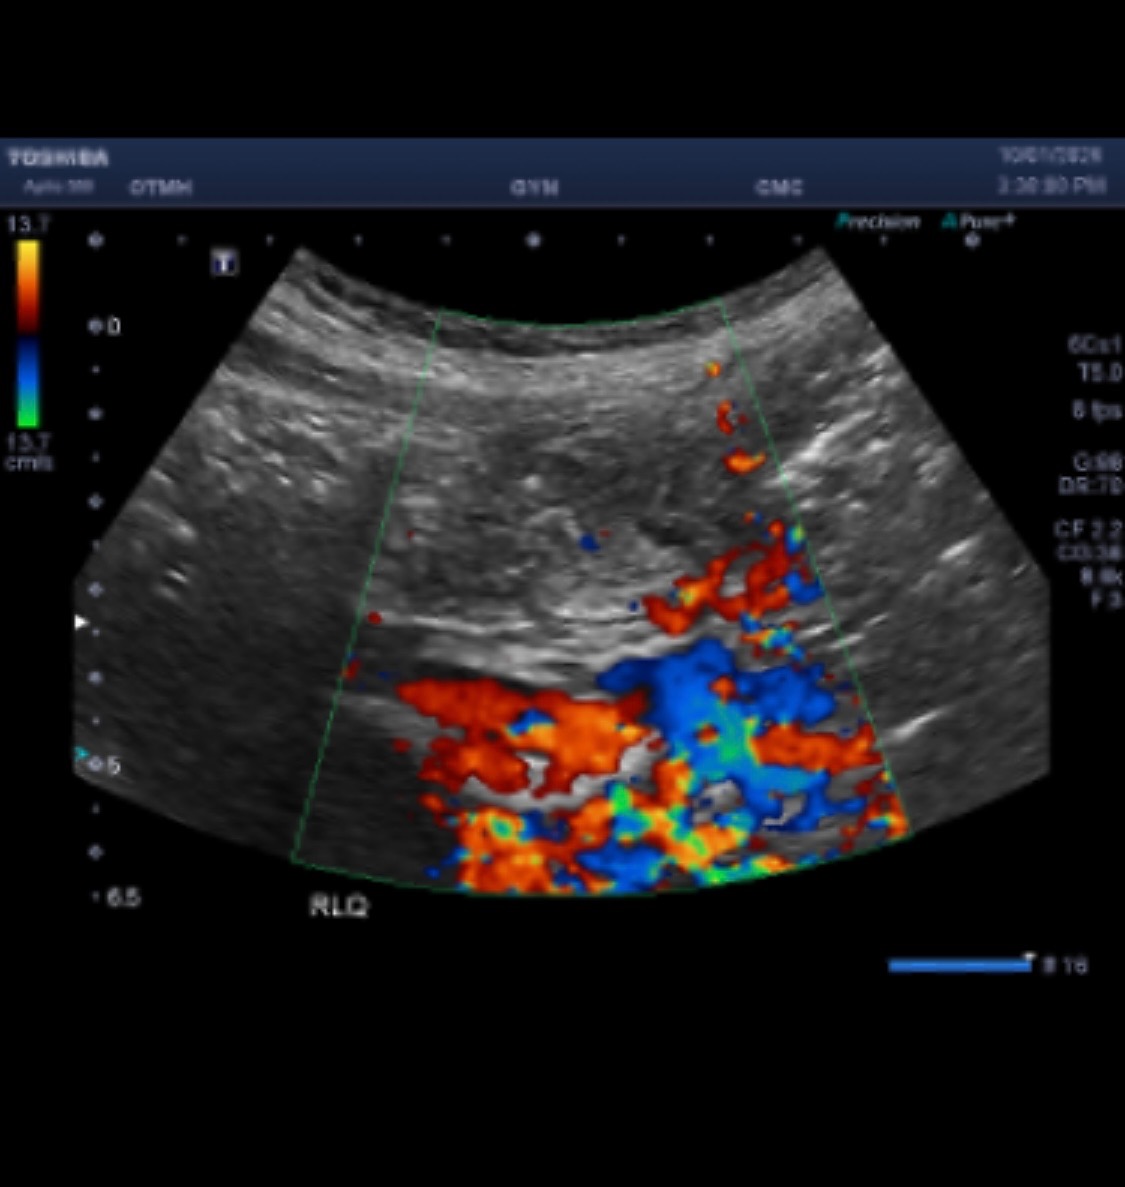

In the summer of 2024, I began to notice differences in my health. I struggled with eating, began losing weight, hair and having pains in my abdomen that would not subside. I was fatigued, passing out, and the smallest of activities felt like a marathon. After months, the pain and fatigue became unbearable, resulting in an emergency hospital visit. After a week of hospitalization, the day after my 25th birthday, I was diagnosed with colon cancer. It has by far been the hardest battle of my entire life, not only physically and emotionally, but also financially. Just having recently graduated and struggling to find consistency in my life, the bills continue to pile up as I battle this disease. Not only does this cause me a world of stress, but also slows down my recovery.